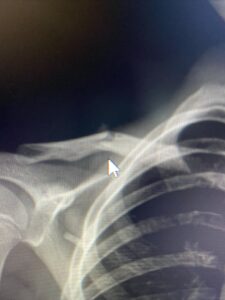

We saw a few broken bones in our office this week as well. You can see in pictures above, the broken ribs on the elderly patient (left) and the broken collar bone on the 6 year old (right). We use a similar protocol to support bone issues such and osteopenia and osteoporosis along with broken bones.